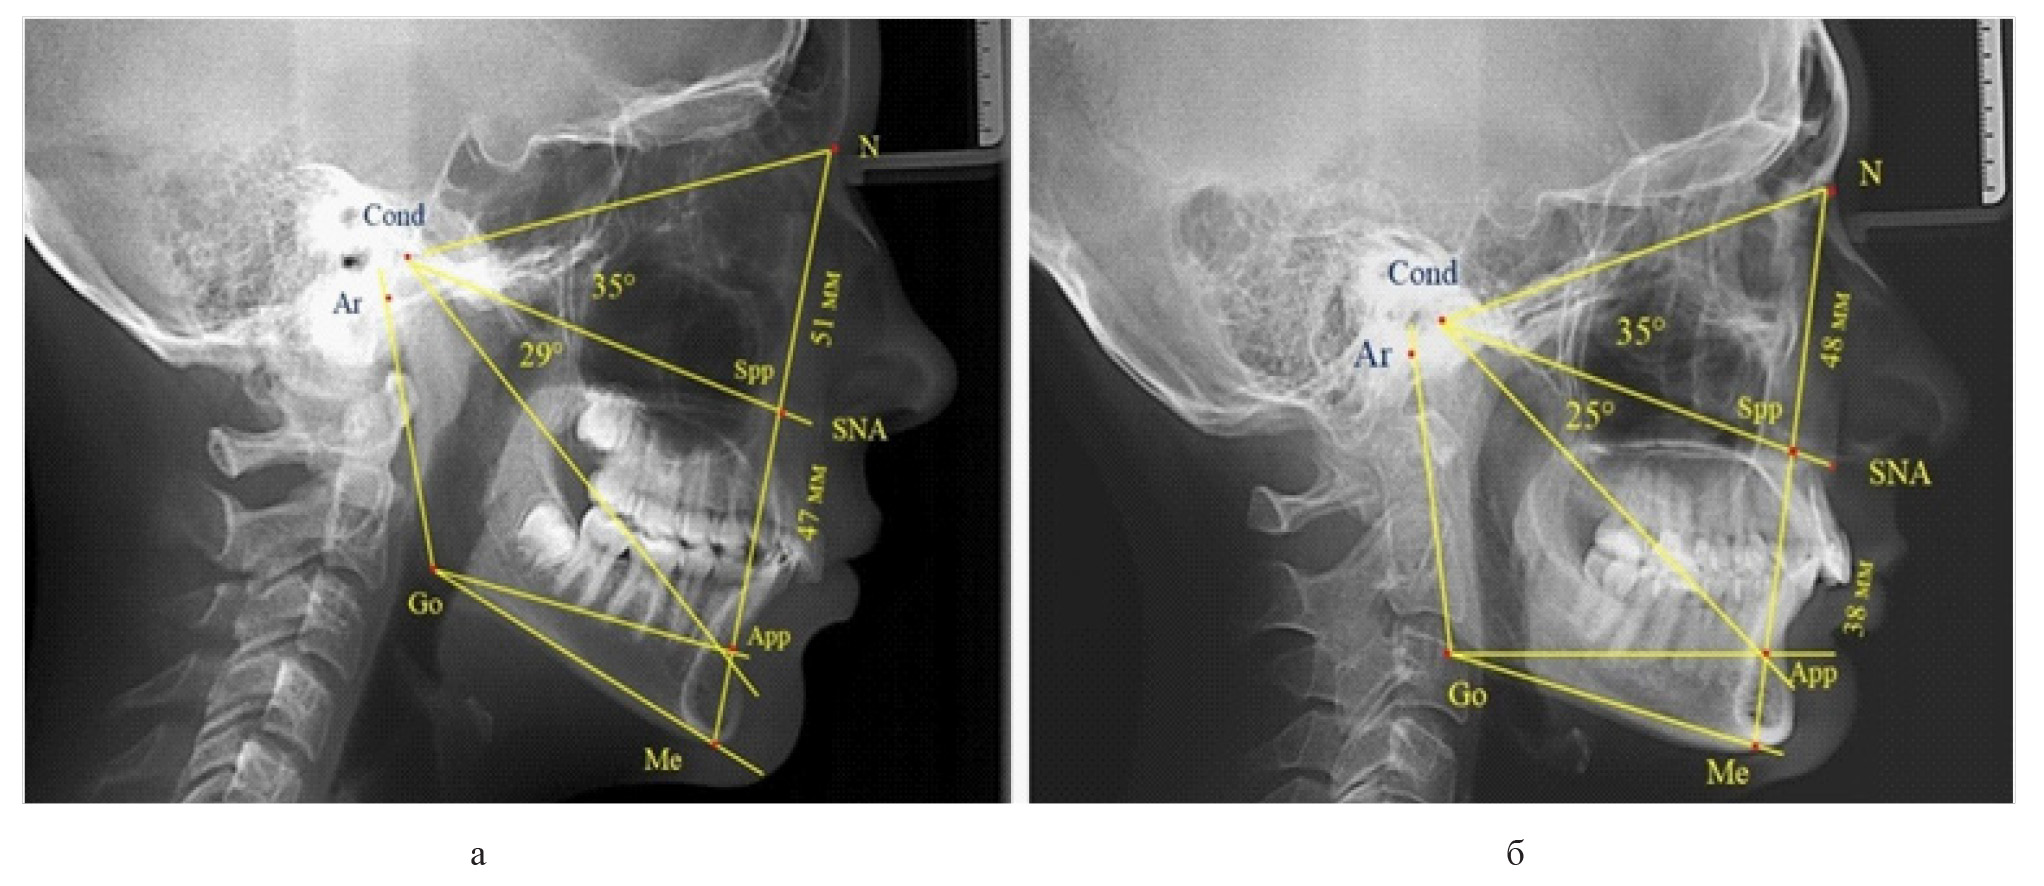

Вертикальная линия передней высоты лица (N-Me), после ее пересечения с линией Cond-SNA, определяла положение точки Spp, при этом вертикаль N-Spp использовалась в качестве оценки высоты назального отдела лица. Продолжение линии Go-Api до пересечения с линией N-Me позволяла определить положение конструктивной точки Арр и оценить линейные размеры гнатической части лица по величине вертикали Spp-Арр (рис. 1).

Рис. 1. Методы оценки основных параметров ТРГ для определения вертикальных размеров лицевого отдела головы

Рис. 4. Варианты ТРГ с укороченными размерами носового отдела и оптимальными (а) и укороченными (б) размерами гнатической части

Среди пациентов с аномалиями челюстно-лицевой области в вертикальном направлении у 24 человек определялась глубокая резцовая окклюзия/дизокклюзия (рис. 5).

Рис. 5. Варианты ТРГ с оптимальными размерами носового отдела и оптимальными (а) и укороченными (б) размерами гнатической части лица

При этом только в двух случаях [(8,33 ± 5,64) %], параметры носового и гнатического отдела соответствовали норме. У 9 человек [(37,59 ± 9,88) %], при оптимальных параметрах назального отдела отмечалось уменьшение высоты гнатического отдела, вплоть до патологических показателей.

У людей с глубокой резцовой окклюзией нередко отмечалось изменение параметров носового отдела лица. Так, в 7 случаях было выявлено снижение параметров как носового, так и гнатического отделов лица. У 5 человек [(20,83 ± 8,28) %], отмечалось уменьшение носового отдела лица при оптимальных параметрах гнатического отдела.

В одном случае [(4,17 ± 4,08) %], определялось патологическое увеличение назального отдела лица при уменьшении гнатической его части. Некоторые варианты ТРГ пациентов с глубокой резцовой окклюзией представлены на рис. 6.

Рис. 6. Варианты ТРГ с уменьшенными размерами носового отдела и оптимальными (а) и укороченными (б) размерами гнатической части лица при глубокой резцовой окклюзии